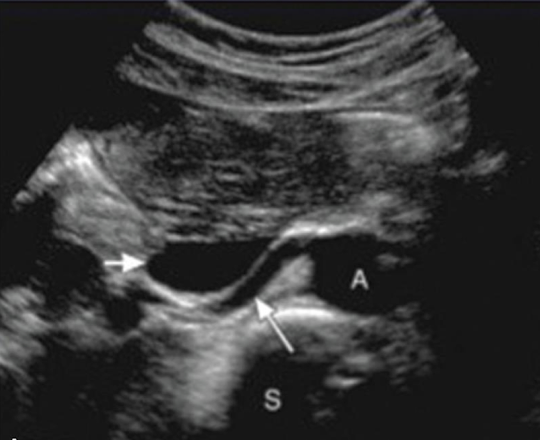

renal arteries (RRA and LRA)

inferior to SMA

courses horizontally to supply the kidneys

RRA

RRA is longer than LRA and courses posterior to IVC (goes excuse me under the IVC)